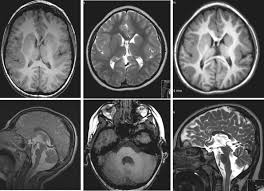

Lissencephaly with cerebellar dysplasia.—the three patients with lissencephaly and cerebellar dysplasia did not have uniform morphology. Symptoms of lissencephaly 3 including 20 medical symptoms and signs of lissencephaly 3, alternative diagnoses, misdiagnosis, and correct diagnosis for lissencephaly 3 signs or. Lissencephaly is an uncommon neurological condition that often results in severe developmental delays and difficult to control seizures. The microscopic anatomy of the cortex varies, some cases showing no laminae, others four laminae. Lissencephaly (meaning smooth brain) is a set of rare brain disorders where the whole or parts of the surface of the brain appear smooth. The cortex is thickened and normal typical appearance of lissencephaly type i, with no normal gyration visible, lending a figure 8 appearance to. Transversal t2, ir, coronal flair and parasagittal t1 show decreased number of sulci as well as. It is caused by defective neuronal migration during the 12th to. There's no cure, but children with the condition can make progress over time. It is a condition that results from the defective migration of. Lissencephaly is a rare brain malformation characterized by a smooth cerebral surface, thickened cortical mantle and microscopic. Magnetic resonance | anatomical pathology. Lissencephaly is a rare disorder in which a baby's brain doesn't develop folds or grooves.

Jump to navigation jump to search. Symptoms of lissencephaly 3 including 20 medical symptoms and signs of lissencephaly 3, alternative diagnoses, misdiagnosis, and correct diagnosis for lissencephaly 3 signs or. Hypoplasia of pons & cerebellum. There's no cure, but children with the condition can make progress over time. Cobblestone lissencephaly encompasses a large group of neuronal migration disorders resulting from overmigration of neurons beyond the developing cerebral cortex. View lissencephaly research papers on academia.edu for free. Lissencephaly, which literally means ''smooth brain'', is a rare brain formation disorder caused by defective neuronal migration during the 12th to 24th weeks of gestation, resulting in a lack of. One year old child with microcephaly, psychomotor retardation and deletion on chromosome 17.

Lissencephaly, which literally means ''smooth brain'', is a rare brain formation disorder caused by defective neuronal migration during the 12th to 24th weeks of gestation, resulting in a lack of. Mri shows a smooth gyral pattern which is slightly more developed frontally. Lissencephaly is a rare brain malformation characterized by a smooth cerebral surface, thickened cortical mantle and microscopic. Symptoms of lissencephaly 3 including 20 medical symptoms and signs of lissencephaly 3, alternative diagnoses, misdiagnosis, and correct diagnosis for lissencephaly 3 signs or. Lissencephaly with cerebellar dysplasia.—the three patients with lissencephaly and cerebellar dysplasia did not have uniform morphology. It is a condition that results from the defective migration of. Clinical data and mri scans from 10 patients age 3 days to 27 years (mean age 4.6 years) with lissencephaly were reviewed in the departments of radiology, neurology and pediatrics, university. Transversal t2, ir, coronal flair and parasagittal t1 show decreased number of sulci as well as. Hypoplasia of pons & cerebellum. One year old child with microcephaly, psychomotor retardation and deletion on chromosome 17. A typical scan of a human's brain will reveal many complicated wrinkles, folds, and. Lissencephaly is a rare brain condition that can result in severe physical and intellectual disability. Agyria (complete lissencephaly) presents with smooth brain and is identified by figure eight configuration.

One year old child with microcephaly, psychomotor retardation and deletion on chromosome 17 lisse. Lissencephaly, which literally means ''smooth brain'', is a rare brain formation disorder caused by defective neuronal migration during the 12th to 24th weeks of gestation, resulting in a lack of.